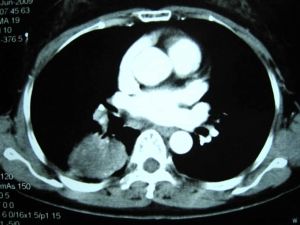

肺癌CT检测未来5年在美国将增加93亿美元市场

最新研究数据显示,美国今年新推出的肺癌检测指南,将在未来5年在CT检测方面带来93亿美元的医疗成本,这对CT检测行业来说,意味着巨大的市场。

在今年年初发布的指南中,美国癌症学会(ACS)和美国预防服务工作组(USPSTF)表示,和普通X光检测相比,CT检测能避免20%肺癌患者死亡。

西雅图Fred Hutchinson癌症研究中心周三发布的报告预测,未来5年将有额外20%的高危人群会接受低剂量CT影像检测,约等于93亿美元的医疗成本,其中56亿美元将用于CT检测,11亿美元用于诊断,26亿美元将用于癌症患者护理。